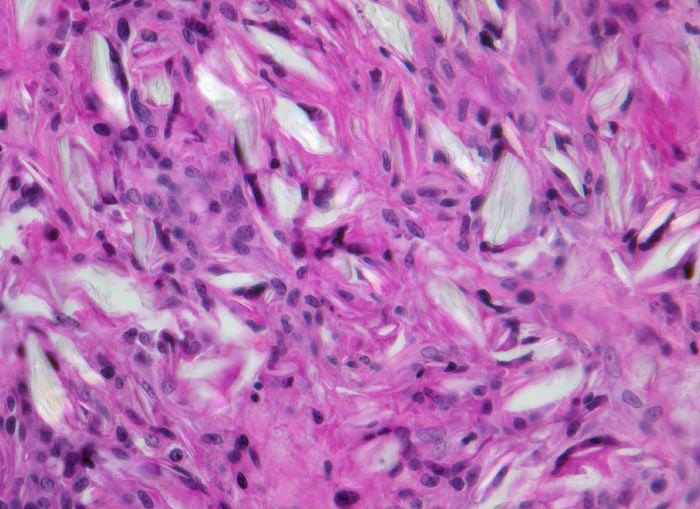

Fremdkörpergranulom

Artefakt / Fremdkörper / Pigment

Weichteile

Bindegewebe mit von histiozytärem Entzündungsinfiltrat und Einschlüssen von amorphem leuchtendem von Fremdmaterial, welches teilweise von Fremdkörperriesenzellen eingeschlossen ist.

Wegen fehlenden klinischen Angaben zu vorausgegangenen Operationen kann die Natur des Fremdmaterials nicht sicher angegeben werden.

320